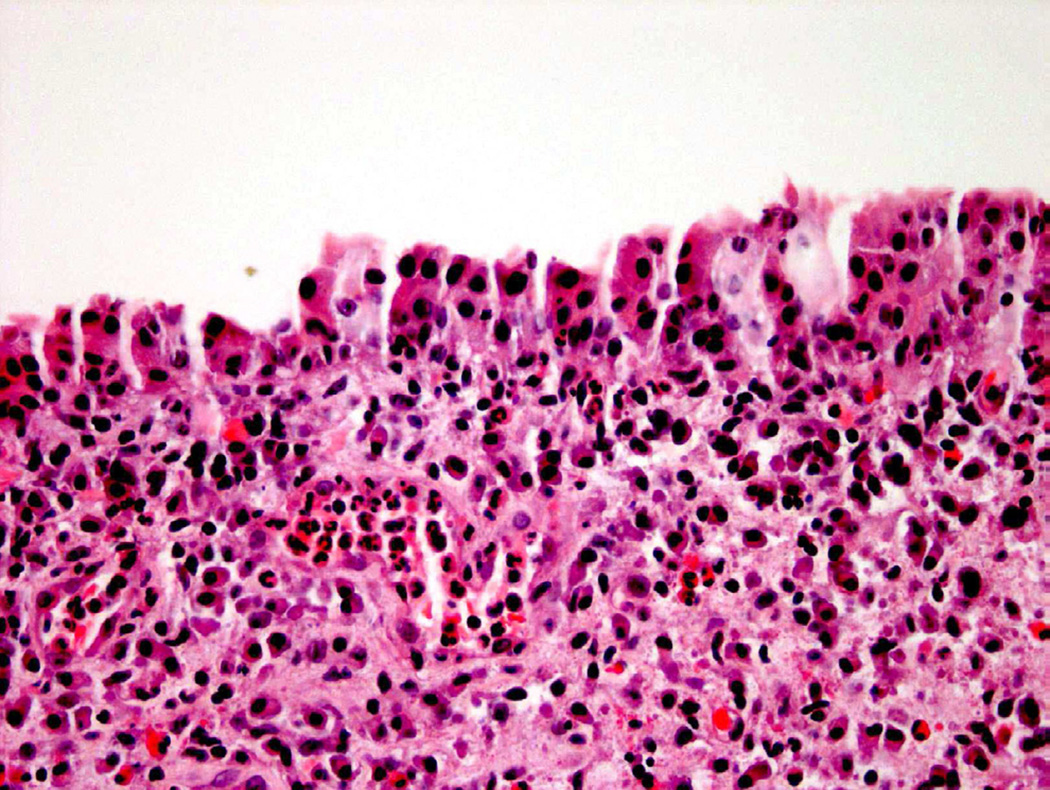

Carcinoma in Situ

Urothelial carcinoma in situ (CIS) is a neoplastic diagnosis, with malignant cells restricted within the urothelial lining of the bladder (non-invasive disease). In addition to the features of dysplasia, these cells demonstrate marked nuclear and cellular pleomorphism and hyperchromasia (Fig. 6)9. CIS is commonly underdiagnosed when full-thickness cytologic atypia is absent or when umbrella cells are identified. Underdiagnosis of CIS may also occur in the setting of “clinging” CIS (single carcinoma cells are present in a background of otherwise denuded urothelium) and subtle involvement of von Brunn nests by CIS cells9.

Figure 6.

CIS typically shows overt neoplastic features.